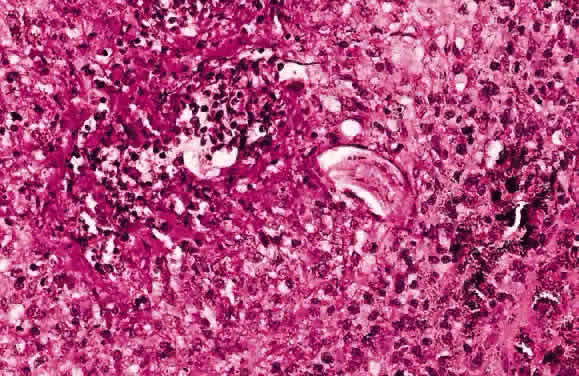

HISTOLOGY AND ULTRASTRUCTURE